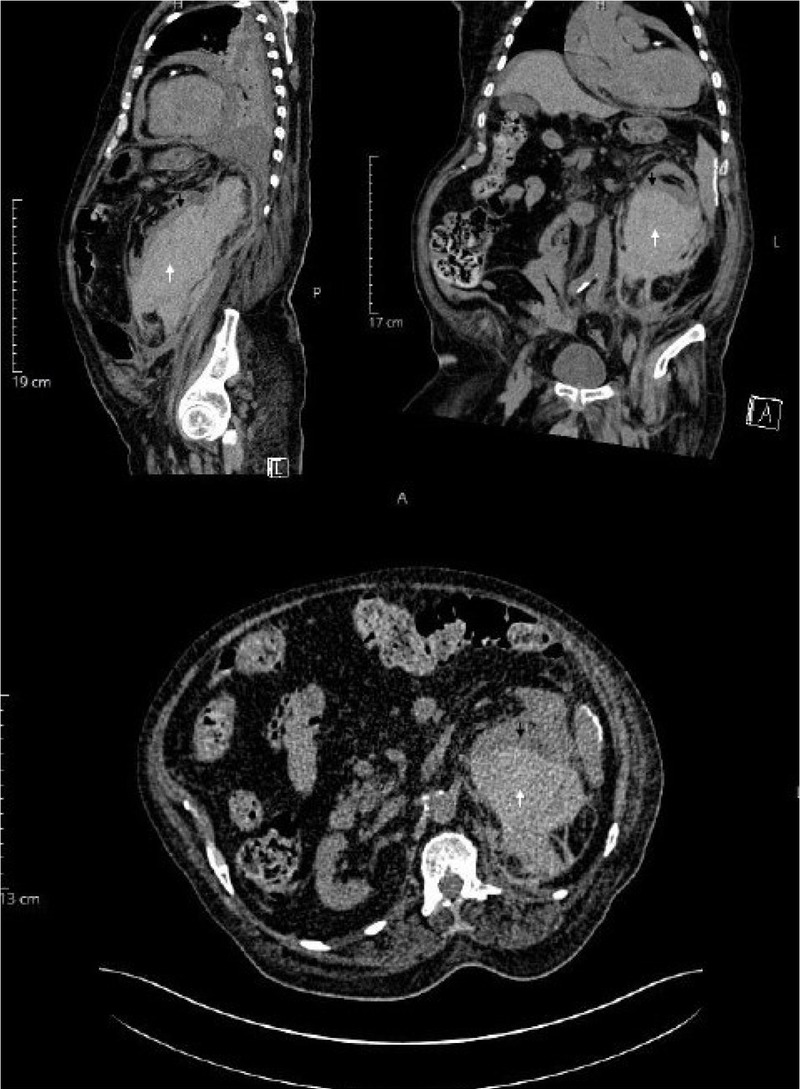

The patient required another 3 units of packed red cell transfusions in our hospital after admission. He subsequently underwent an ultrasound abdomen that revealed a significant collection around the left kidney (Figure 1). A CT abdomen without contrast was arranged due to his AKI and it revealed a 10 cm × 8 cm perinephric hematoma, which had completely distorted the renal mass and the cortex (Figure 2).

CT abdomen (non-contrast) showing hematoma in the renal mass (white arrow) with distortion of the renal cortex (black arrow) in the sagittal (top-left), coronal (top-right) and transverse (bottom) planes.